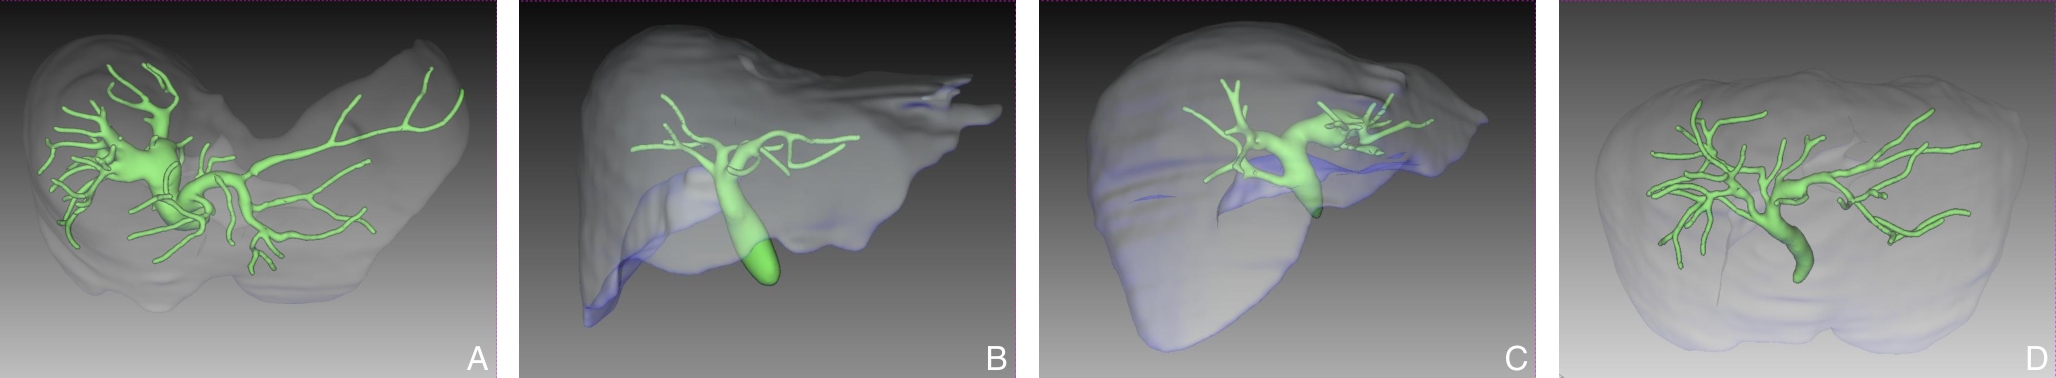

• Clinical application of three-dimensional visualization technology in assessing the spatial configuration of major hepatic vessels and liver lobar volume distribution

2026, 35(1):124-140. DOI: 10.7659/j.issn.1005-6947.250635

Abstract (93) HTML (137) PDF 3.82 M (171) Comment (0) Favorites

Abstract:Background and Aims The hepatic vascular and biliary systems exhibit substantial anatomical variability and complex spatial relationships, posing challenges for precise surgical planning based on conventional two-dimensional imaging. This study aimed to evaluate the clinical value of three-dimensional visualization in characterizing the spatial architecture of hepatic vasculature and bile ducts and to explore its association with hepatic volumetric distribution.Methods A total of 610 living liver donors and 158 patients with bile duct dilatation were retrospectively analyzed. Three-dimensional models of the hepatic artery, portal vein, hepatic veins, and bile ducts were reconstructed from contrast-enhanced CT images. Vascular and biliary anatomical patterns, spatial relationships, and their correlations with hepatic lobe and segmental volumes were systematically assessed.Results Three-dimensional visualization enabled intuitive and comprehensive depiction of hepatic vascular and biliary anatomy. Distinct portal vein configurations were associated with significant differences in regional liver volume distribution, with an increased proportion of the right posterior lobe observed in patients with specific portal vein branching patterns. The presence of an inferior right hepatic vein with a diameter ≥5 mm was also associated with a larger right posterior lobe volume. Analyses of extrahepatic and intrahepatic spatial relationships revealed relatively consistent positional patterns between the right hepatic artery, portal vein, and bile ducts, and a significant correlation was observed between the spatial courses of the right hepatic artery and the right posterior bile duct.Conclusion Three-dimensional visualization provides accurate preoperative assessment of hepatic vascular and biliary anatomy and clarifies complex spatial relationships and their volumetric implications. This technique offers critical anatomical support for precision hepatobiliary surgery and liver transplantation.